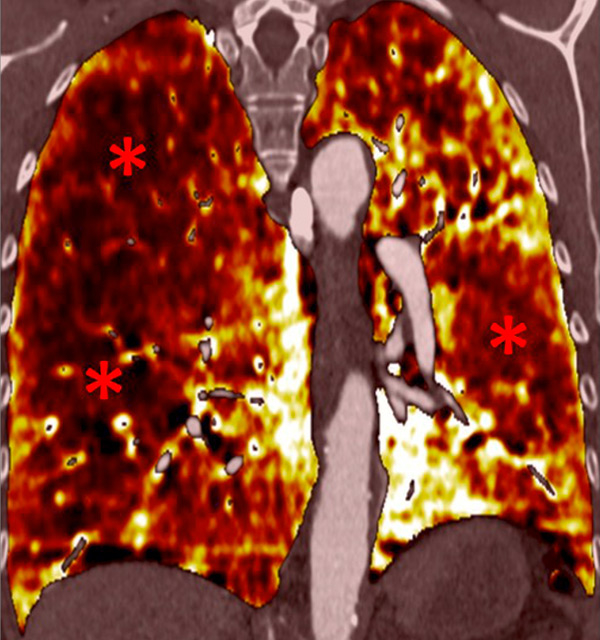

Figure 6

Perfusion heterogeneities in idiopathic pulmonary artery hypertension (stars) in two different patients (A/B). The dilatation of the arteries in pulmonary hypertension (arrows) is not always observed depending on the severity of pulmonary hypertension.